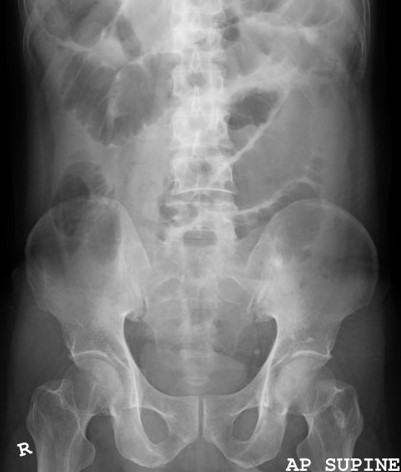

Neurofibromatosis (NF) is a genetic neurological disorder which can lead to abnormal tumour suppression. Neurofibromatosis associated neurological tumour is usually benign in nature, only occasionally can become malignant. Gastrointestinal involvement is reported to be infrequent with only up to 25% of patients with neurofibromatosis showing involvement. Solitary gastrointestinal neurofibroma is very rare, with most cases involving the stomach or small bowel. We report here a case of solitary small intestinal neurofibroma with no other associated systemic signs, causing intussusception and intestinal obstruction.